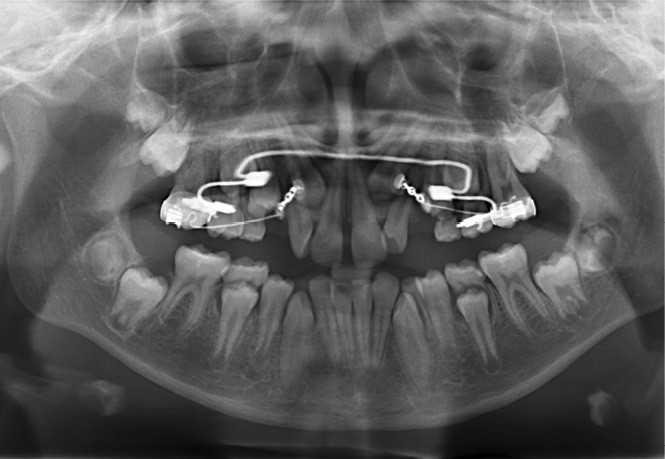

Sur la radiographie panoramique, on observe une transposition des canines maxillaires en place d’incisives latérales, au contact des racines de 11 et 21.

À ce stade, une radiographie panoramique est réalisée pour s’assurer de l’intégrité des racines, contrôler les axes dentaires et planifier le repositionnement de certaines attaches ainsi que le collage des tubes sur les secondes molaires en cours d’éruption.